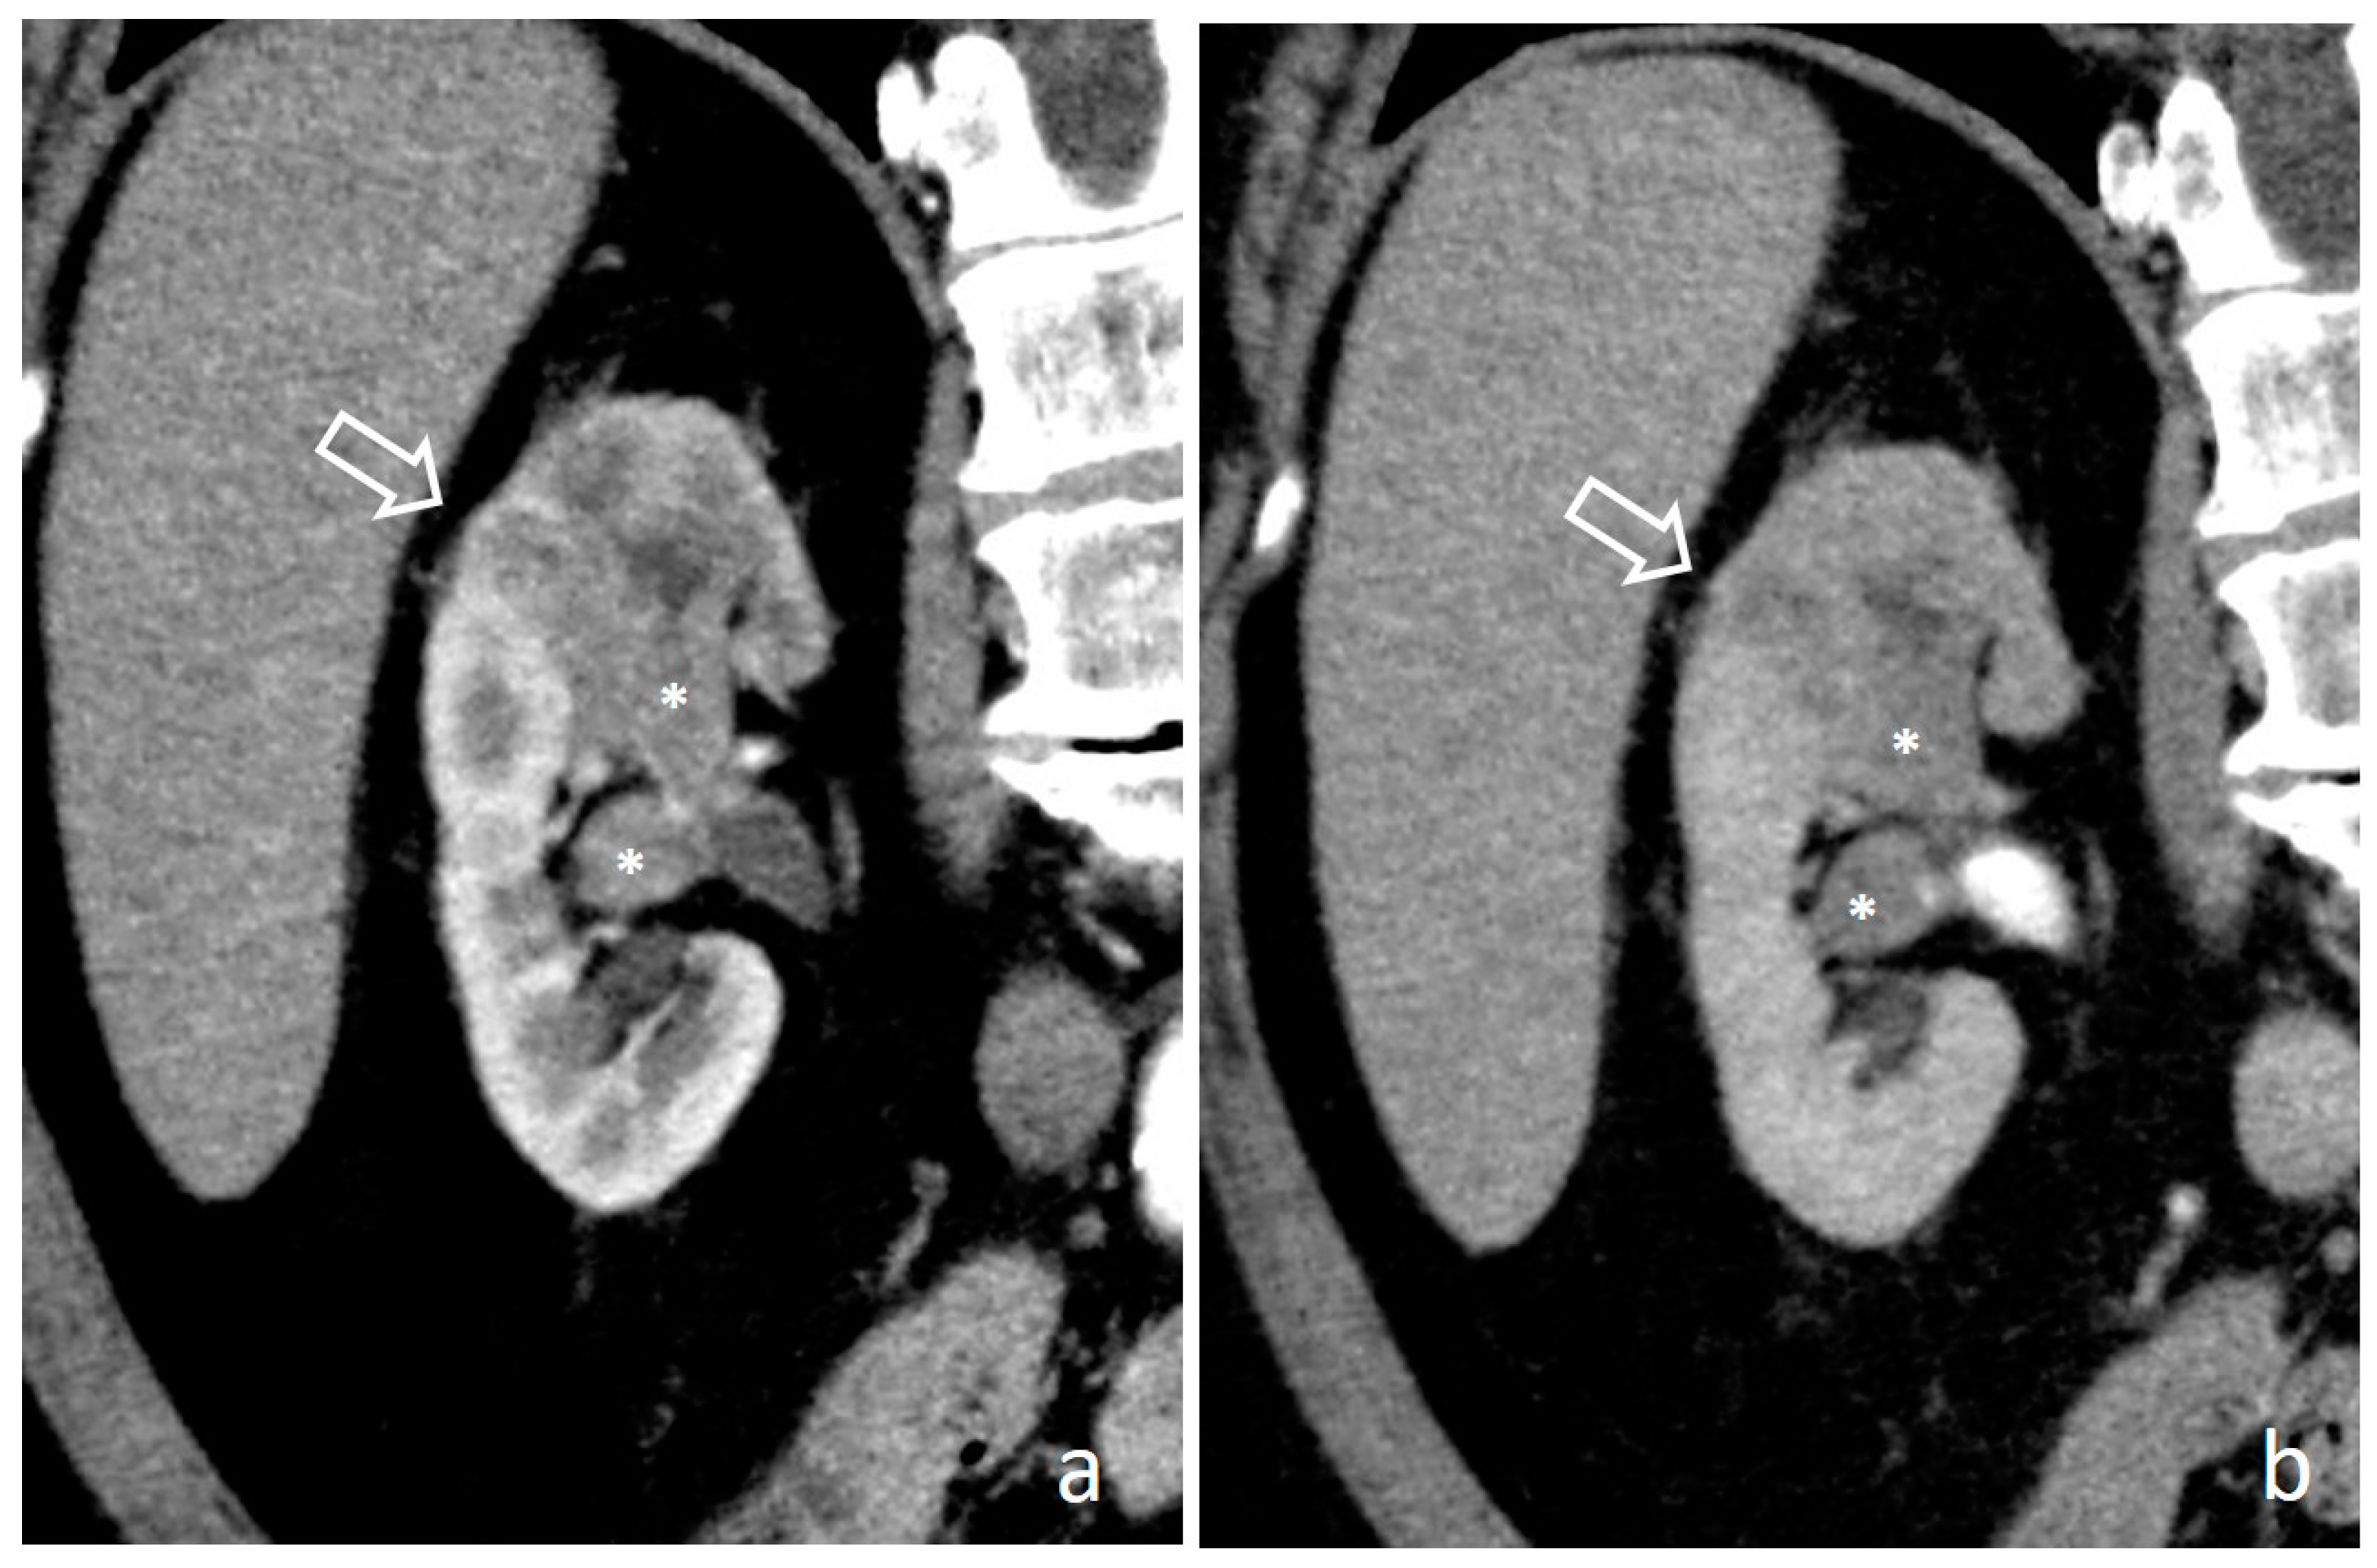

4.10. Renal Cell Carcinoma

4.11. Renal Lymphoma